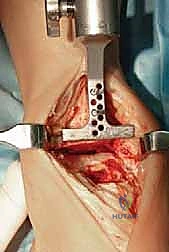

3. إزالة الأسطح التالفة (تحضير العظام)

باستخدام أدوات جراحية دقيقة وموجهات خاصة، يتم إزالة الغضاريف التالفة وجزء رقيق جداً من العظام المريضة من نهايتي عظمة الظنبوب وعظمة الكاحل (Talus). يتم تشكيل العظام بدقة لتتطابق تماماً مع شكل أجزاء المفصل الصناعي.

4. تركيب المفصل الصناعي (Implantation)

يتكون مفصل الكاحل الصناعي الحديث عادة من ثلاثة أجزاء:

* قطعة معدنية علوية: تُثبت في عظمة الظنبوب (الساق).

* قطعة معدنية سفلية: تُثبت في عظمة الكاحل.

* قطعة بلاستيكية (بولي إيثيلين عالي الكثافة): توضع بين القطعتين المعدنيتين لتنزلق بسلاسة وتمتص الصدمات، محاكيةً وظيفة الغضروف الطبيعي.

يتم تثبيت هذه الأجزاء بإحكام (إما عن طريق الضغط المباشر لتشجيع نمو العظم حولها، أو باستخدام أسمنت طبي خاص).